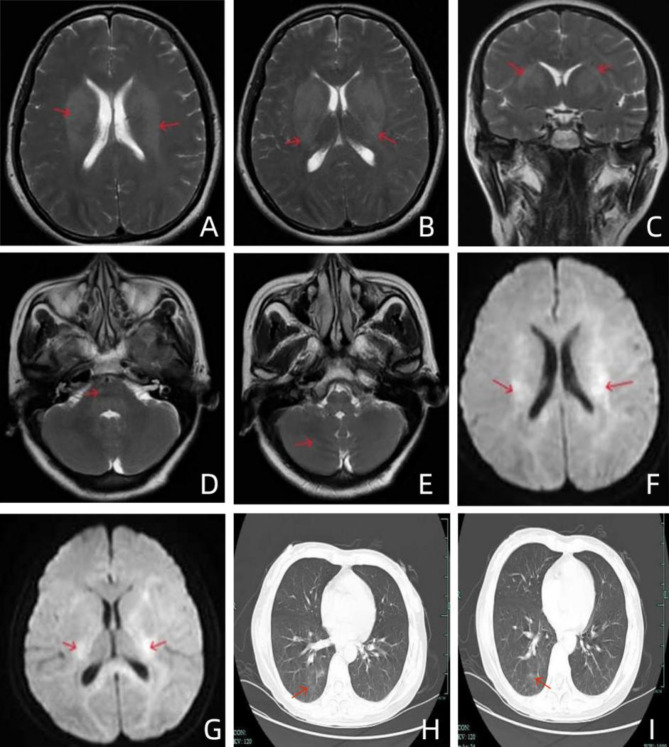

Background: Central nervous system (CNS) involvement in diffuse large B-cell lymphoma (DLBCL) is relatively rare, occurring at a rate of approximately 5%. Primary CNS lymphoma (CNS-DLBCL), a subtype of DLBCL, is rare clinically but highly malignant and invasive. Its atypical clinical symptoms and imaging features contribute to a high rate of misdiagnosis and a poor prognosis. Thus, early and accurate diagnosis is imperative for improving the patient's prognosis. Cerebrospinal fluid (CSF) cytology, a rapid and convenient diagnostic method, plays a crucial role in diagnosing intracranial tumors.

Case presentation: In this instance, the patient presented with nonspecific early symptoms and exhibited atypical imaging findings. A lumbar puncture performed at another hospital yielded a low cell count in the CSF, leading to an incorrect diagnosis. Upon admission to our hospital, CSF cytology identified abnormal cells. A definitive diagnosis of CNS-DLBCL was established utilizing additional diagnostic methods, facilitating targeted treatment.